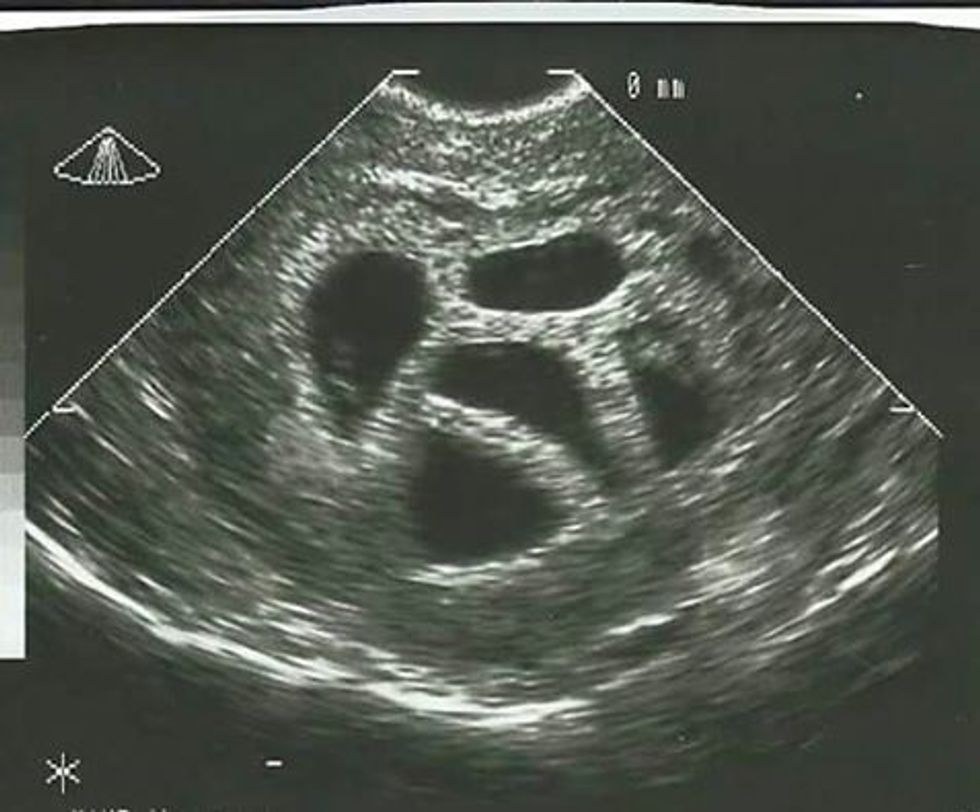

Gjatë kontrolleve mjekësore atë e priste edhe një befasi tjetër. Aty e kuptoi se nuk po e pret vetëm një fëmijë por pesënjakë, transmeton Telegrafi.